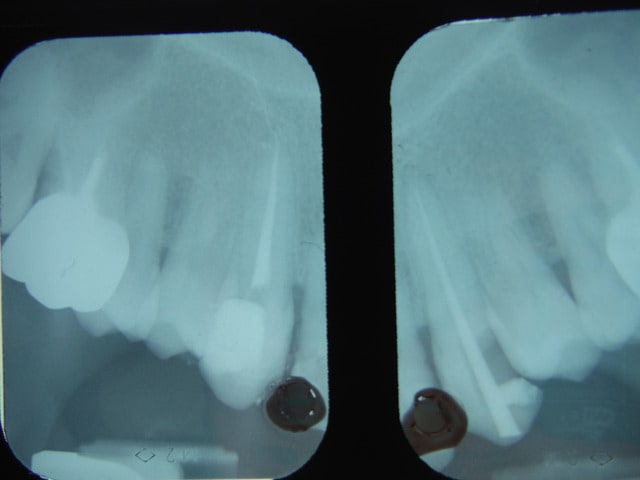

Juste pour l'anecdote, un ancien cas (argentique), j’espère que c'est visible . J'ai obturé la gaine nerveuse de cette canine.

Bah même pas mal.

pas autopsié, dent toujours sur arcade.

Je pense que c'est de la pâte, j'ai de temps en temps ce genre d'image, mais là c'est le top du top.

Euh sinon elle propre mon endo, à l'apex.

Très propre... C'est ce qui s'appelle dévitaliser jusqu'au cerveau! :-)

Ca m'arrive aussi d'envoyer du blanc au-delà de l'apex dans un petit canal.